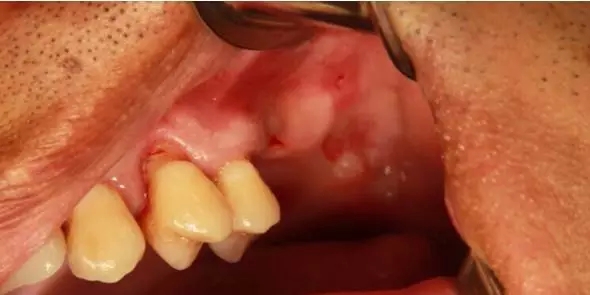

患者50歲,男性,身體健康。左上6,7缺失,骨高度2mm。

術前口內照和CT片。

1.webp.jpg

2.webp.jpg